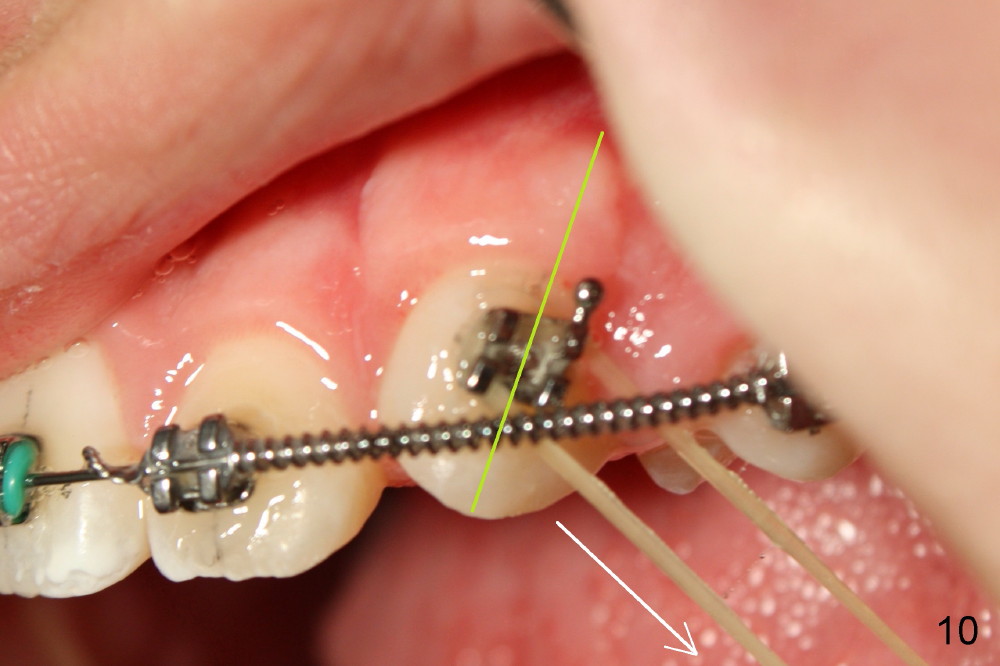

Two months postop, the canines have erupted substantially (Fig. 9 (downward arrow), 10, as compared to Fig.7,8). Since the long axis of the canines is oblique, the patient is instructed to wear elastic downward and backward (Fig.10 oblique arrow).